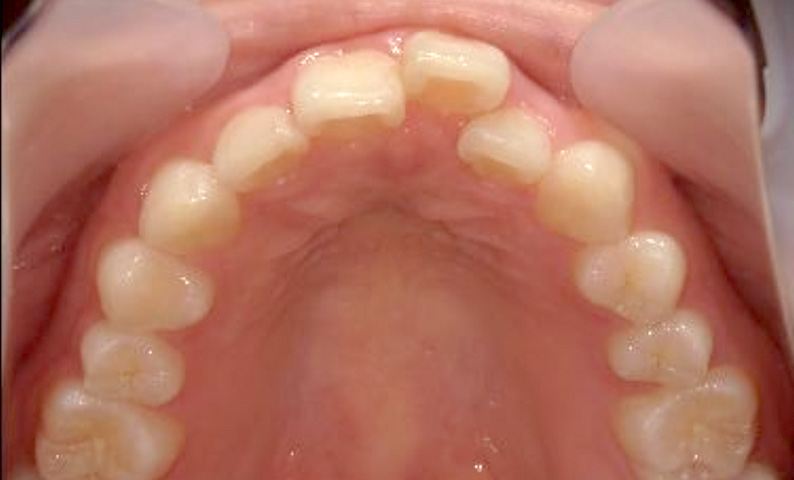

症例_025 上顎だけの部分矯正

治療期間:7ヶ月金額:30万円+税女性前歯のガタガタ上の前歯だけ